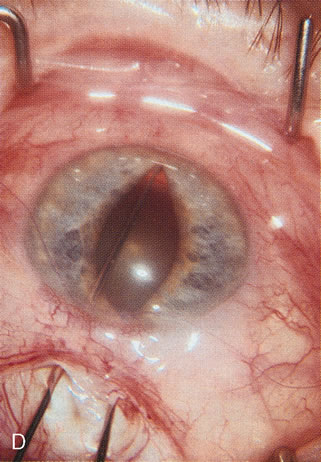

Fig. 3. Partial bleb failure following clear corneal phacoemulsification with foldable IOL. A. Preoperative bleb appearance prior to temporal lens extraction. Preoperative IOP was 12 mm Hg on no antiglaucoma medications. Time from 5-FU trabeculectomy surgery to lens extraction was one year. B. Bleb appearance 2 months after clear corneal cataract surgery with topical anesthesia. Following lens extraction, increased vascularity was noted along with decreased size of the filtering bleb. IOP increased to 20 mm Hg as early as 2 weeks after surgery, necessitating topical antiglaucoma therapy. C. High magnification view of bleb before lens extraction demonstrates diffuse pale bleb. D. High magnification view of bleb 2 months after surgery. There are vessels surrounding the nasal side of the bleb and the overall bleb size is smaller.

Cataract extraction by any technique performed in a patient with a pre-existing filter will have an effect on the previous filtering bleb.121–124 Bleb failure is more likely with ECCE compared with small-incision phacoemulsification.125 However, even patients undergoing topical anesthesia with clear corneal phacoemulsification and foldable IOL may experience bleb failure. One of three patients with a functioning filter and preoperative mean IOP of 12 mm Hg without antiglaucoma medications experiences bleb failure after lens extraction (Table 2). These patients require long-term drug therapy or bleb needling to control IOP. 126 Additional incisional glaucoma surgery may eventually be required in up to 10% of patients.127 Intraoperative iris manipulation may cause significant breakdown of the blood–aqueous barrier, resulting in inflammation that causes bleb failure. Even after uncomplicated clear corneal phacoemulsification, IOP may increase an average of 2 to 3 mm Hg due to bleb fibrosis.128 Approximately 20% of filtered patients require a long-term increase in glaucoma medications following uncomplicated clear corneal phacoemulsification with a foldable copolymer acrylic IOL129 (Fig. 3). In situations in which the bleb is not working at all, the eye will have a postoperative pressure spike that mimics that in the patient not having had a prior filtering procedure. In situations in which the bleb is marginal, the pressure spikes tend to be lower, and the final postoperative IOP tends to be around 50% higher than it was preoperatively. These patients require combined procedures in order to reestablish long-term filtration. In situations in which the bleb is very thin, polycystic, and associated with an IOP around 5 to 8 mm Hg on no antiglaucoma therapy; uncomplicated cataract extraction will have a minimal effect on the level of IOP. Patients with functioning glaucoma drainage implants usually have minimal long-term changes in IOP after uncomplicated cataract extraction.130